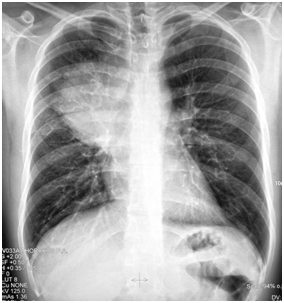

The 1st case we report is of a 22-year-old Caucasian male, who was admitted to our hospital with a 3-days history of progressive dyspnea on exertion, neck swelling, fatigue, persistent chest pain, pyrexia, and a cough that was occasionally productive of blood. The physical examination revealed a heart rate of 115 beats per minute (Sinus Rhythm), a respiratory rate of 25 breaths per minute and superficial vascular distention over the neck. Laboratory studies revealed elevated serum α-fetoprotein (AFP) (5380 IU/ml) and D-dimer (481ng/ml). A chest X-ray in the poster - anterior view, upon admission, depicted a suggestive right upper mediastinal mass (Bild 1). Radiography was followed by contrast-enhanced CT scan that revealed a large, homogeneous mediastinal mass crossing into the anterior mediastinum and compressing – encasing the superior vena cava. It also showed signs of thrombosis of the left brachiocephalic vein, and multiple filling defects at the left pulmonary artery indicating embolism. Subcarinal lymphadenopathy, as well as enlarged lymph nodes of the right hilum was present (Bild’s 2-5). On median sternotomy, a large non resectable tumor was observed involving the in nominate vein and the superior vena cava (Bild 6). Great care was taken to remove as much tumor mass as possible. To decompress the superior vena cava, we had to perform an extensive resection and reconstruction of the cephalad part of the superior vena cava using homolog pericardium.A histopathological examination of a section of the mass revealed a mixed NSGCT (embryonal yolk sac/endodermal sinus tumour), containing also elements of embryonal carcinoma (Figure 1-6).The patient was placed on cisplatin-based chemotherapy (BEP regimen: cisplatin 50mg/m2 on days 1-2, etoposide 165mg/m2 on days 1-3, bleomycin 30U on days 1, 8, and 15, every 3 weeks). Tumor markers were elevated for a-FP (214ng/mL) and normal for β-HCG. The patient completed 4 cycles of chemotherapy and the subsequent chest CT (Bild 7) revealed a partial remission of the mass (decrease>50% of the size). The a-FP was normal as well as the β-HCG. The remaining mass was inoperable so the patient was started on salvage chemotherapy with the TIP (paclitaxel, ifosfamide, ciplatin) regimen for 4 cycles. The post-chemo chest CT showed stable disease and the patient was referred to radiation oncologists for radiotherapy of the remaining tumor. Three months later af P was found elevated and the CTs revealed multiple brain metastases. Whole brain radiation was performed and the patient was placed on gemcitabine (d1 and d8 every 21 days). Two months later the neurologic status deteriorated with new brain metastases and the patient passed away (19 months after the diagnosis).

Bild 5 CT –coronar plan of a Yolk sac tumor (yellow arrow) invading and occluding the vena cava superior (red arrow).